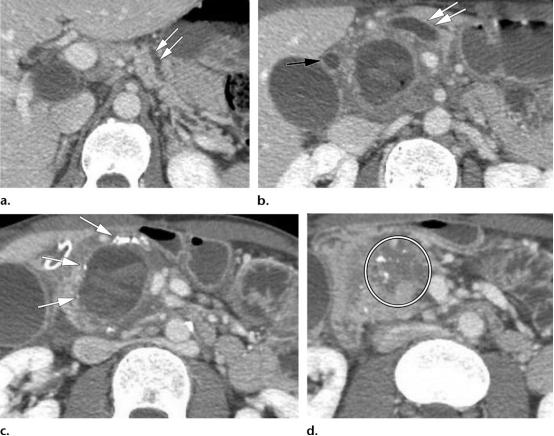

43岁男性,肿块形成型慢性胰腺炎,伴假性囊肿。

(a图,b图)轴位CT示主胰管弥漫增粗(两个平行排列的白色双箭头)以及扩张的胆总管(黑色长箭头),这也称为*管双**征。胰腺实质保存完好,胰管与胰腺实质的比值小于0.5。

(c图)轴位CT图示胰头区散在钙化灶(白色长箭头),在胰头区域可见囊性病变,伴血性内容物,符合假性囊肿表现。

(d图)轴位CT图示胰头区肿块样增大(白色圆圈)